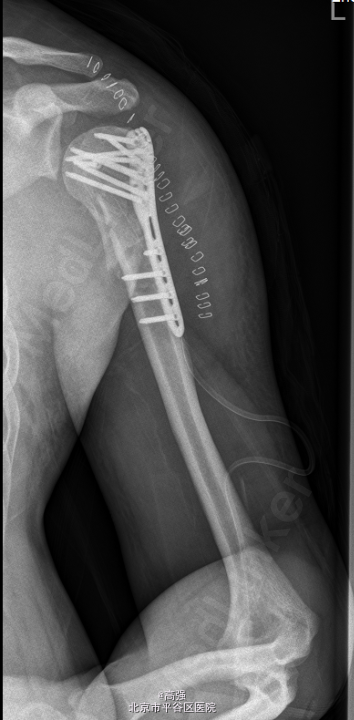

初步诊断: 左肱骨近端粉碎性骨折 行左肱骨骨折切复内固定术